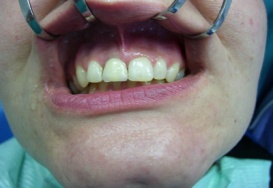

Klasickým příkladem a indikací pro použití implantátu je ztráta jednoho zubu (v tomto případě v předním – frontálním úseku) v jinak zdravém, nepoškozeném chrupu.

Nejčastější příčinou takové ztráty je sportovní nebo dopravní úraz.

Náhrada jednoho zubu pomocí implantátu je možná také v postranním úseku chrupu. Při ztrátě většího počtu zubů ve frontálním nebo postranním úseku může být mezer uzavřena větším počtem jednotlivých implantátů.

Při ošetření pomocí jednotlivých implantátů zůstávají sousední zuby neporušené – intaktní. Při klasickém ošetření pomocí můstků musejí být tyto zuby obroušeny!